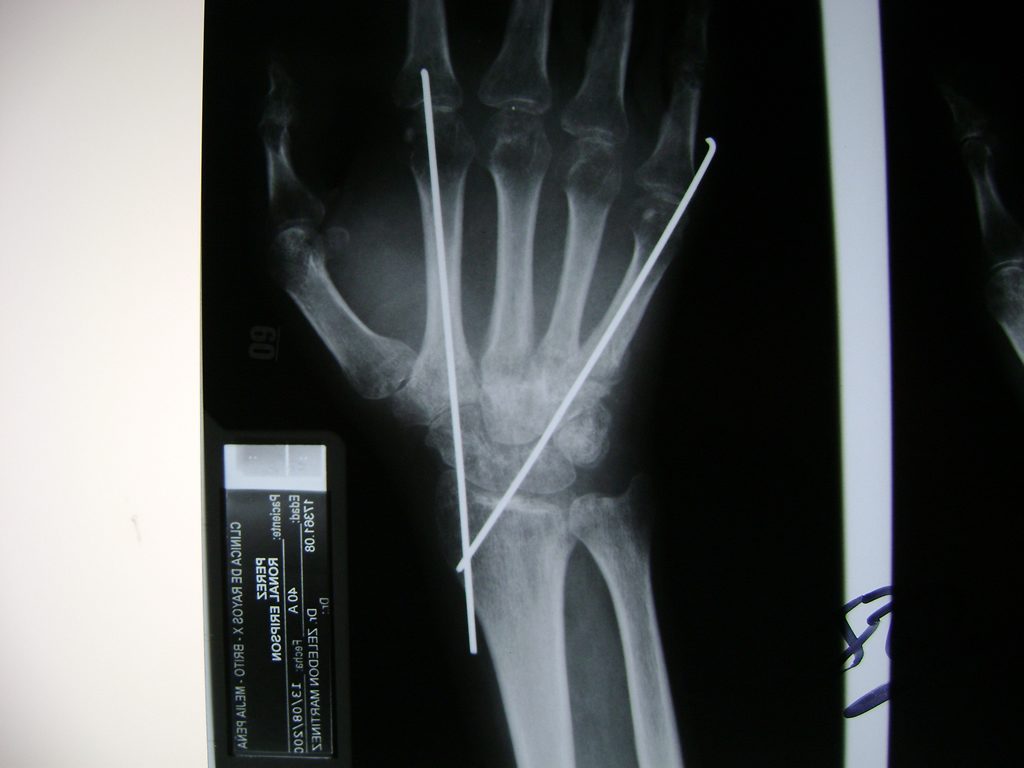

Cirugía de Fémur - Cirugías de Muñecas y Manos

Los procedimientos más comunes en cirugía de la mano son aquellos destinados a reparar traumatismos, incluyendo lesiones de tendones, nervios, vasos sanguíneos, y articulaciones; huesos fracturados; y quemaduras, cortes, y otros daños de la piel.